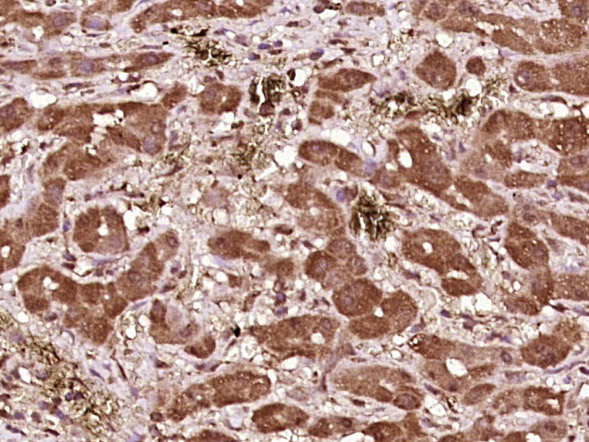

| 英文名称 | phospho-BAD (Ser99) Rabbit pAb |

| 中文名称 | 磷酸化相关死亡促进因子抗体 |

| 产品应用 | IHC-P=1:100-500, IHC-F=1:100-500, IF=1:100-500 Not yet tested in other applications. |

| {IHC-P} | {1:100-500} |